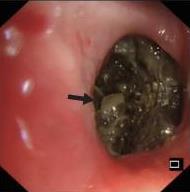

摘要:目的 探讨侵袭性肺真菌病(IPFD)的支气管镜表现,并评估介入治疗的安全性和疗效。方法 回顾性分析2018年5月12日-2025年5月12日于该院行支气管镜检查的35例IPFD患者的临床资料,观察IPFD的支气管镜表现及介入治疗效果。结果 共收集35例患者临床资料。其中,男22例,女13例,患者年龄(53±14)岁。基础疾病包括:血液系统恶性肿瘤10例,长期应用糖皮质激素者5例,2型糖尿病者4例,肺部恶性肿瘤2例,器官移植1例。胸部CT显示:肺部病变累及单肺叶者19例,累及多肺叶者16例。支气管镜下表现主要为:黏膜充血水肿29例(82.9%)、坏死物堵塞管腔22例(62.9%)、大量黏稠脓性分泌物17例(48.6%)、支气管部分狭窄或闭塞16例(45.7%)、黏膜坏死9例(25.7%)、黏膜出血5例(14.3%)、真菌球3例(8.6%)。其中,32例(91.4%)接受全身性抗真菌治疗,17例(48.6%)接受支气管镜局部两性霉素B灌注治疗,10例(28.6%)采用活检钳钳除病灶,6例(17.1%)采用冷冻探头冻取病灶,4例(11.4%)接受氩气刀治疗。28例(80.0%)临床症状明显改善,肺部影像学病灶缩小或消退;4例(11.4%)病灶稳定;3例(8.6%)未完成治疗。结论 IPFD多见于免疫抑制宿主,支气管镜常表现为:坏死物堵塞管腔、伴脓性分泌物、支气管管腔狭窄和局部黏膜充血水肿或坏死。全身抗真菌药物联合支气管镜下介入治疗,安全性高,且疗效好。